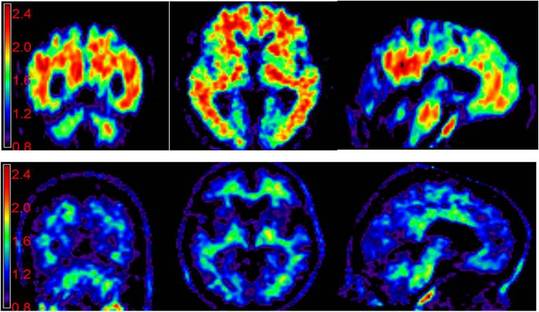

A cintilografia de perfusão cerebral é um método utilizado por clínicos médicos especializados em doenças relacionadas ao SNC (Sistema Nervoso Central) para detectar enfermidades que afetam a função do cérebro. E quando o assunto se refere à doenças neurológicas, o principal nome é a depressão.

O exame, conhecido também como spect, permite avaliar a função cerebral através do fluxo sanguíneo. Um radiofármaco, ou seja, uma substância químico-radioativa, é injetada na veia do paciente e permite que um aparelho radiográfico obtenha imagens coloridas do cérebro. O radiofármaco utilizado não provoca nenhum dano à saúde, mas esse exame não é recomendado para gestantes, visto que o feto fica exposto à radiação.

Logo após o repouso, que geralmente dura trinta minutos, tempo suficiente para que o radiofármaco circule por todas as regiões do cérebro, o paciente é conduzido até a sala de exames radiográficos para a aquisição dos fotogramas do cérebro. As imagens obtidas pelo aparelho indicarão quais regiões estão trabalhando menos do que o normal. Sabe-se que a depressão atinge mais os lobos frontais, ou seja, a região mais à frente do cérebro, que fica logo acima dos olhos. A partir dessa informação, o especialista é auxiliado pelos fotogramas na hora de diagnosticar o paciente.

O Dr. Whemberton também fala sobre o uso do exame: “O emprego da cintilografia de perfusão cerebral se baseia no paralelismo que ocorre na grande maioria dos casos entre perfusão, metabolismo e função cerebral. A oferta de oxigênio e de glicose, através do fluxo sanguíneo no cérebro, para cada região é proporcional à necessidade metabólica. Esta, por sua vez, é determinada pela intensidade da atividade neuronal. Baseado num banco de dados, a cintilografia compara cérebros saudáveis de voluntários com o do paciente e, a partir disso, verifica-se qual região está funcionando normalmente e qual não está.”